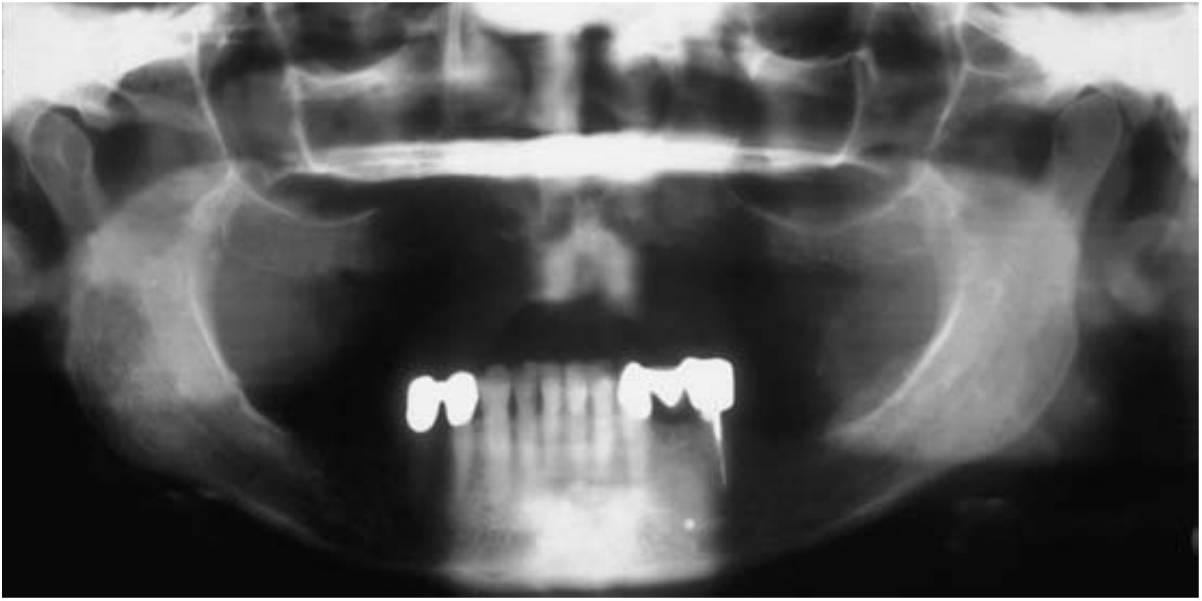

Los huesos necesitan estímulo para mantener su forma y densidad. Roberts y cols, dedujeron que una compresión del 4 % sobre el sistema esquelético mantiene el hueso y ayuda en el equilibrio del fenómeno de reabsorción y formación. Los dientes transmiten las fuerzas de compresión y tensión al hueso circundante. Estas fuerzas se han medido como un efecto piezoeléctrico en los cristales imperfectos de la hidroxiapatita que compone la porción inorgánica del hueso. Al perder un diente, la falta de estimulación en el hueso residual provoca una disminución de la densidad ósea y trabecular en el área, con pérdida del ancho externo, y por tanto de la altura, del volumen óseo. Hay una disminución del 2 5 % en la anchura del hueso durante el primer año posterior a la pérdida del diente y una pérdida de altura toral de 4 mm durante el año siguiente a una extracción en una dentadura inmediata. En un estudio longitudinal de 25 años en pacientes edéntulos, las cefalografías laterales mostraron pérdidas continuas de hueso durante este período de tiempo; se observó una pérdida cuatro veces mayor en la mandíbula65 (fig. 1-14). En cualquier caso, y debido a que la altura mandibular inicial es el doble que la maxilar, la pérdida ósea maxilar también es significativa a largo plazo en el paciente edéntulo.

Un diente es necesario para el desarrollo del hueso alveolar, y se necesita la estimulación de este hueso para mantener su densidad y volumen. Una dentadura removible (parcial o completa) no estimula ni mantiene el hueso; más bien acelera la pérdida ósea. La carga de la masticación se transmite solo a la superficie del hueso, y no a todo el hueso. Como resultado, el aporte sanguíneo disminuye y se produce la pérdida de volumen óseo total. Este asunto, que es de máxima importancia, ha sido observado pero no tratado por la odontología tradicional en el pasado. Los facultativos suelen mirar con indiferencia la pérdida ósea insidiosa que se producirá después de una extracción dentaria. El paciente no suele ser informado acerca de los cambios anatómicos y de las potenciales consecuencias de la continua pérdida ósea. La pérdida ósea se acentúa cuando el paciente lleva una prótesis parcial mucosoportada mal encajada. El paciente no sabe que se va perdiendo hueso en el transcurso del tiempo y a un mayor promedio debajo de una dentadura mal ajustada (fig. 1-15). Los pacientes no vuelven para revisiones regulares para evaluar su estado; en su lugar, vuelven varios años después cuando su dentadura se ha degradado o ya no la pueden tolerar. De ahí que los métodos tradicionales de sustitución de las piezas dentales afecten con frecuencia a la pérdida ósea de una manera no lo suficientemente considerada por el facultativo y el paciente. El facultativo debería informar al paciente de que la dentadura sustituye más al hueso y a los tejidos blandos que a los dientes, y que cada 5 años es conveniente llevar a cabo un rebasado protésico o la colocación de una nueva dentadura para sustituir la pérdida ósea adicional debida a la atrofia (fig. 1-16).

Los rebordes edéntulos atrofiados se asocian a problemas anatómicos que suelen deteriorar los resultados predecibles de las técnicas de odontología tradicionales (fig. 1-17).